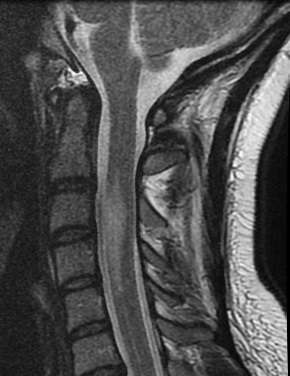

La infarto de la médula espinal es una condición clínica relativamente infrecuente, que generalmente se presenta en el territorio de la arteria espinal anterior. Esta arteria es responsable del suministro sanguíneo de los dos tercios anteriores de la médula espinal y está irrigada por un número limitado de arterias afluentes. La interrupción del flujo sanguíneo en una o más de estas arterias puede resultar en un infarto, lo cual puede ser provocado por diversas condiciones patológicas, como la disección aórtica, el aneurisma aórtico, la aortografía, la poliarteritis, la hipotensión severa o como consecuencia de la reparación quirúrgica de la aorta torácica o abdominal.

A diferencia de la arteria espinal anterior, las arterias espinales posteriores reciben su irrigación de un mayor número de arterias que se distribuyen a lo largo de diferentes niveles de la médula espinal. Esta diferencia en el suministro vascular es significativa, ya que la hipoperfusión de la médula espinal puede llevar a un síndrome de cordón central, que se caracteriza por debilidad distal de tipo motoneuronal inferior y pérdida de la apreciación del dolor y la temperatura, mientras que la función de los cordones posteriores permanece preservada.

Dado que la arteria espinal anterior tiene numerosos afluentes en la región cervical, los infartos relacionados con esta arteria tienden a ocurrir en segmentos más caudales de la médula espinal. La presentación clínica de un infarto de médula espinal se caracteriza por un inicio agudo de paraplejía flácida y areflexiva. Este cuadro clínico evoluciona, después de unos días o semanas, hacia una paraplejía espástica acompañada de respuestas plantares extensores. Además, se observa una pérdida sensorial disociada, donde hay una alteración en la percepción del dolor y la temperatura, mientras que las sensaciones de vibración y la percepción de la posición articular permanecen intactas.